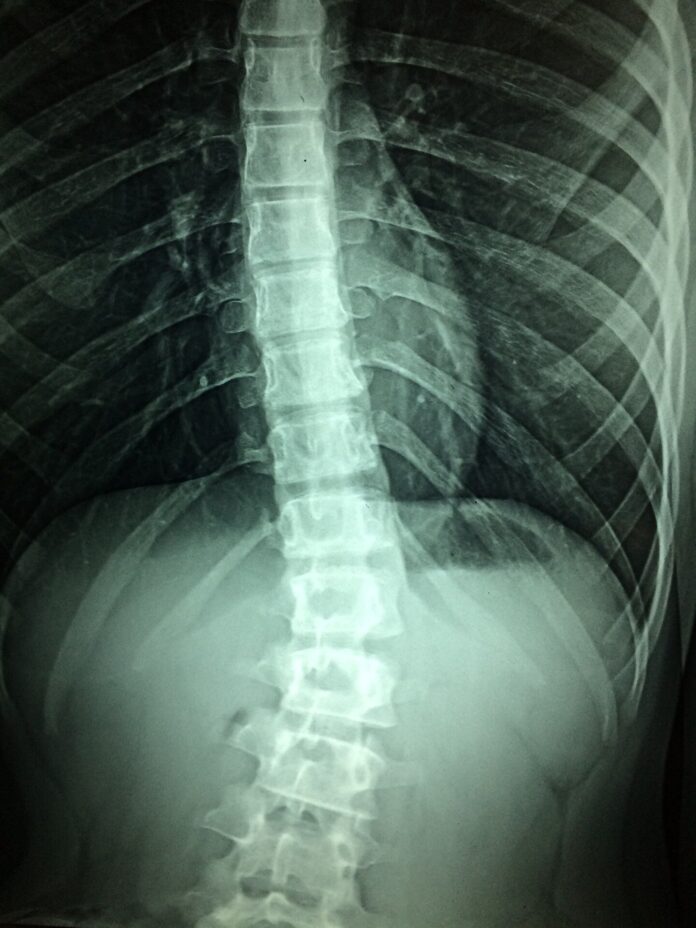

Optogenetic mouse model aids study of limb spasticity after spinal cord...